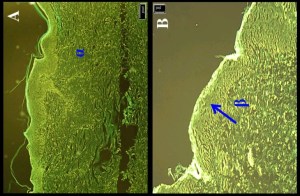

One of these profiles is not like the others. This is Figure 3 from Ahmad et al (2020c) [22], “Different FT–IR spectra with an ATR attachment of BUD, PLGA, PVA, chitosan, physical mixture, and freeze-dried CS-coated-BUD–PLGA–NPs”, and it is where I first encountered Ahmad’s work. One of the spectra appears to be a Medieval map of the fjords of the Norwegian coastline.

The lowermost spectrum is BUD, plain Budesonide in the absence of nanoparticles to facilitate its delivery to the lungs, and it does not seem to have been plotted with the same equipment used for the NPs or their precursors. This record FT-IRs cannot be played plotted on old tin boxes no matter what they are fitted with. If you are in possession of such equipment please hand it into the nearest police station. The first author did offer an explanation to critics in the PubPeer thread, though whether it is satisfactory is another question.

Other than the palsied quavery overhanging nature of the curve, the lack of any strong link between the wavenumbers labeling the fjords and the horizontal axis remains to be explained.